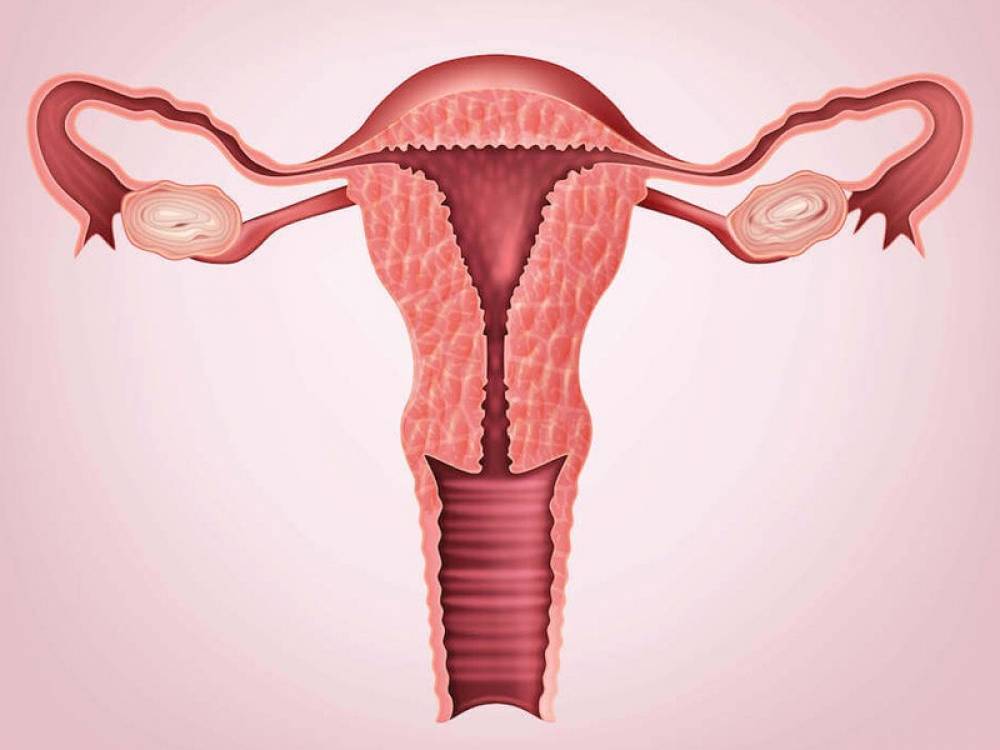

فیبرومهای رحمی از شایعترین تومورهای خوشخیم در زنان در سن باروری هستند که میتوانند باعث علائم ناخوشایندی مانند خونریزیهای شدید قاعدگی، درد لگن و مشکلات باروری شوند. در حالی که درمانهای پزشکی و جراحی برای فیبروم وجود دارد، اخیراً توجه به مداخلات غیرتهاجمی مانند ورزش به عنوان یک روش مکمل افزایش یافته است. این مقاله به بررسی نقش ورزش در مدیریت فیبرومهای رحمی، مکانیسمهای اثرگذاری و بهترین انواع فعالیتهای ورزشی برای این منظور میپردازد.

ورزش می تواند تاثیر بسیاری بر درمان فیبروم رحم داشته باشد. بیایید ابتدا ببینیم ورزش برای درمان فیبروم رحم، چگونه بر فیبروم تاثیر میگذارد.